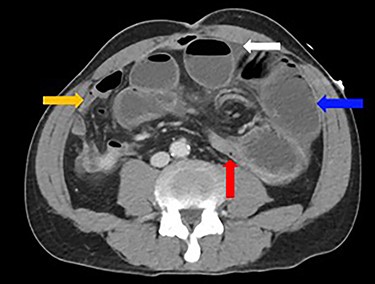

Dilated loops of small bowel (blue arrow), transition point (red arrow), free fluid (evidence of CA; white arrow) and collapsed small bowel (orange arrow).

A 52-year-old man presented with a 1-day history of generalized abdominal pain, distension and vomiting. Two years prior, he underwent a subtotal colectomy for colorectal cancer associated with Lynch syndrome and adjuvant chemotherapy. He was haemodynamically stable on presentation. Examination revealed a soft abdomen with marked distension and left periumbilical tenderness, however, no peritonism. Biochemistry showed lactate: 1.9, white cell count: 17 and C-reactive protein: 10. Computed tomography (CT) abdomen demonstrated a closed-loop SBO with transition point mid-abdomen, free fluid but no free gas (Figs 1 and 2). The patient was resuscitated with intravenous fluids, a nasogastric tube was inserted and they proceeded to an exploratory laparotomy for the closed-loop SBO. Intra-operative findings noted a loop of distended small bowel adherent to the anterior abdominal and pelvis side walls, with a loop of ileum twisted at the mesentery secondary to a band adhesion causing the closed-loop obstruction. The patient underwent adhesiolysis and untwisting of the mesentery, which demonstrated viable ileum with no evidence of perforation. In addition, the liver was smooth, there was no evidence of peritoneal metastases and the previous side-to-side ileo-sigmoid anastomosis was intact with no evidence of stricture or cancer recurrence. Lastly, milky intra-abdominal fluid was noted intra-operatively, with a sample sent for biochemistry showing a triglyceride level of 1584 mg/dl indicative of CA. Post-operative recovery was delayed by a prolonged ileus for which they were commenced on total parenteral nutrition (TPN) and slowly upgraded to a low-fat diet following resolution of the ileus. They were discharged home on Day 49 post-operatively.